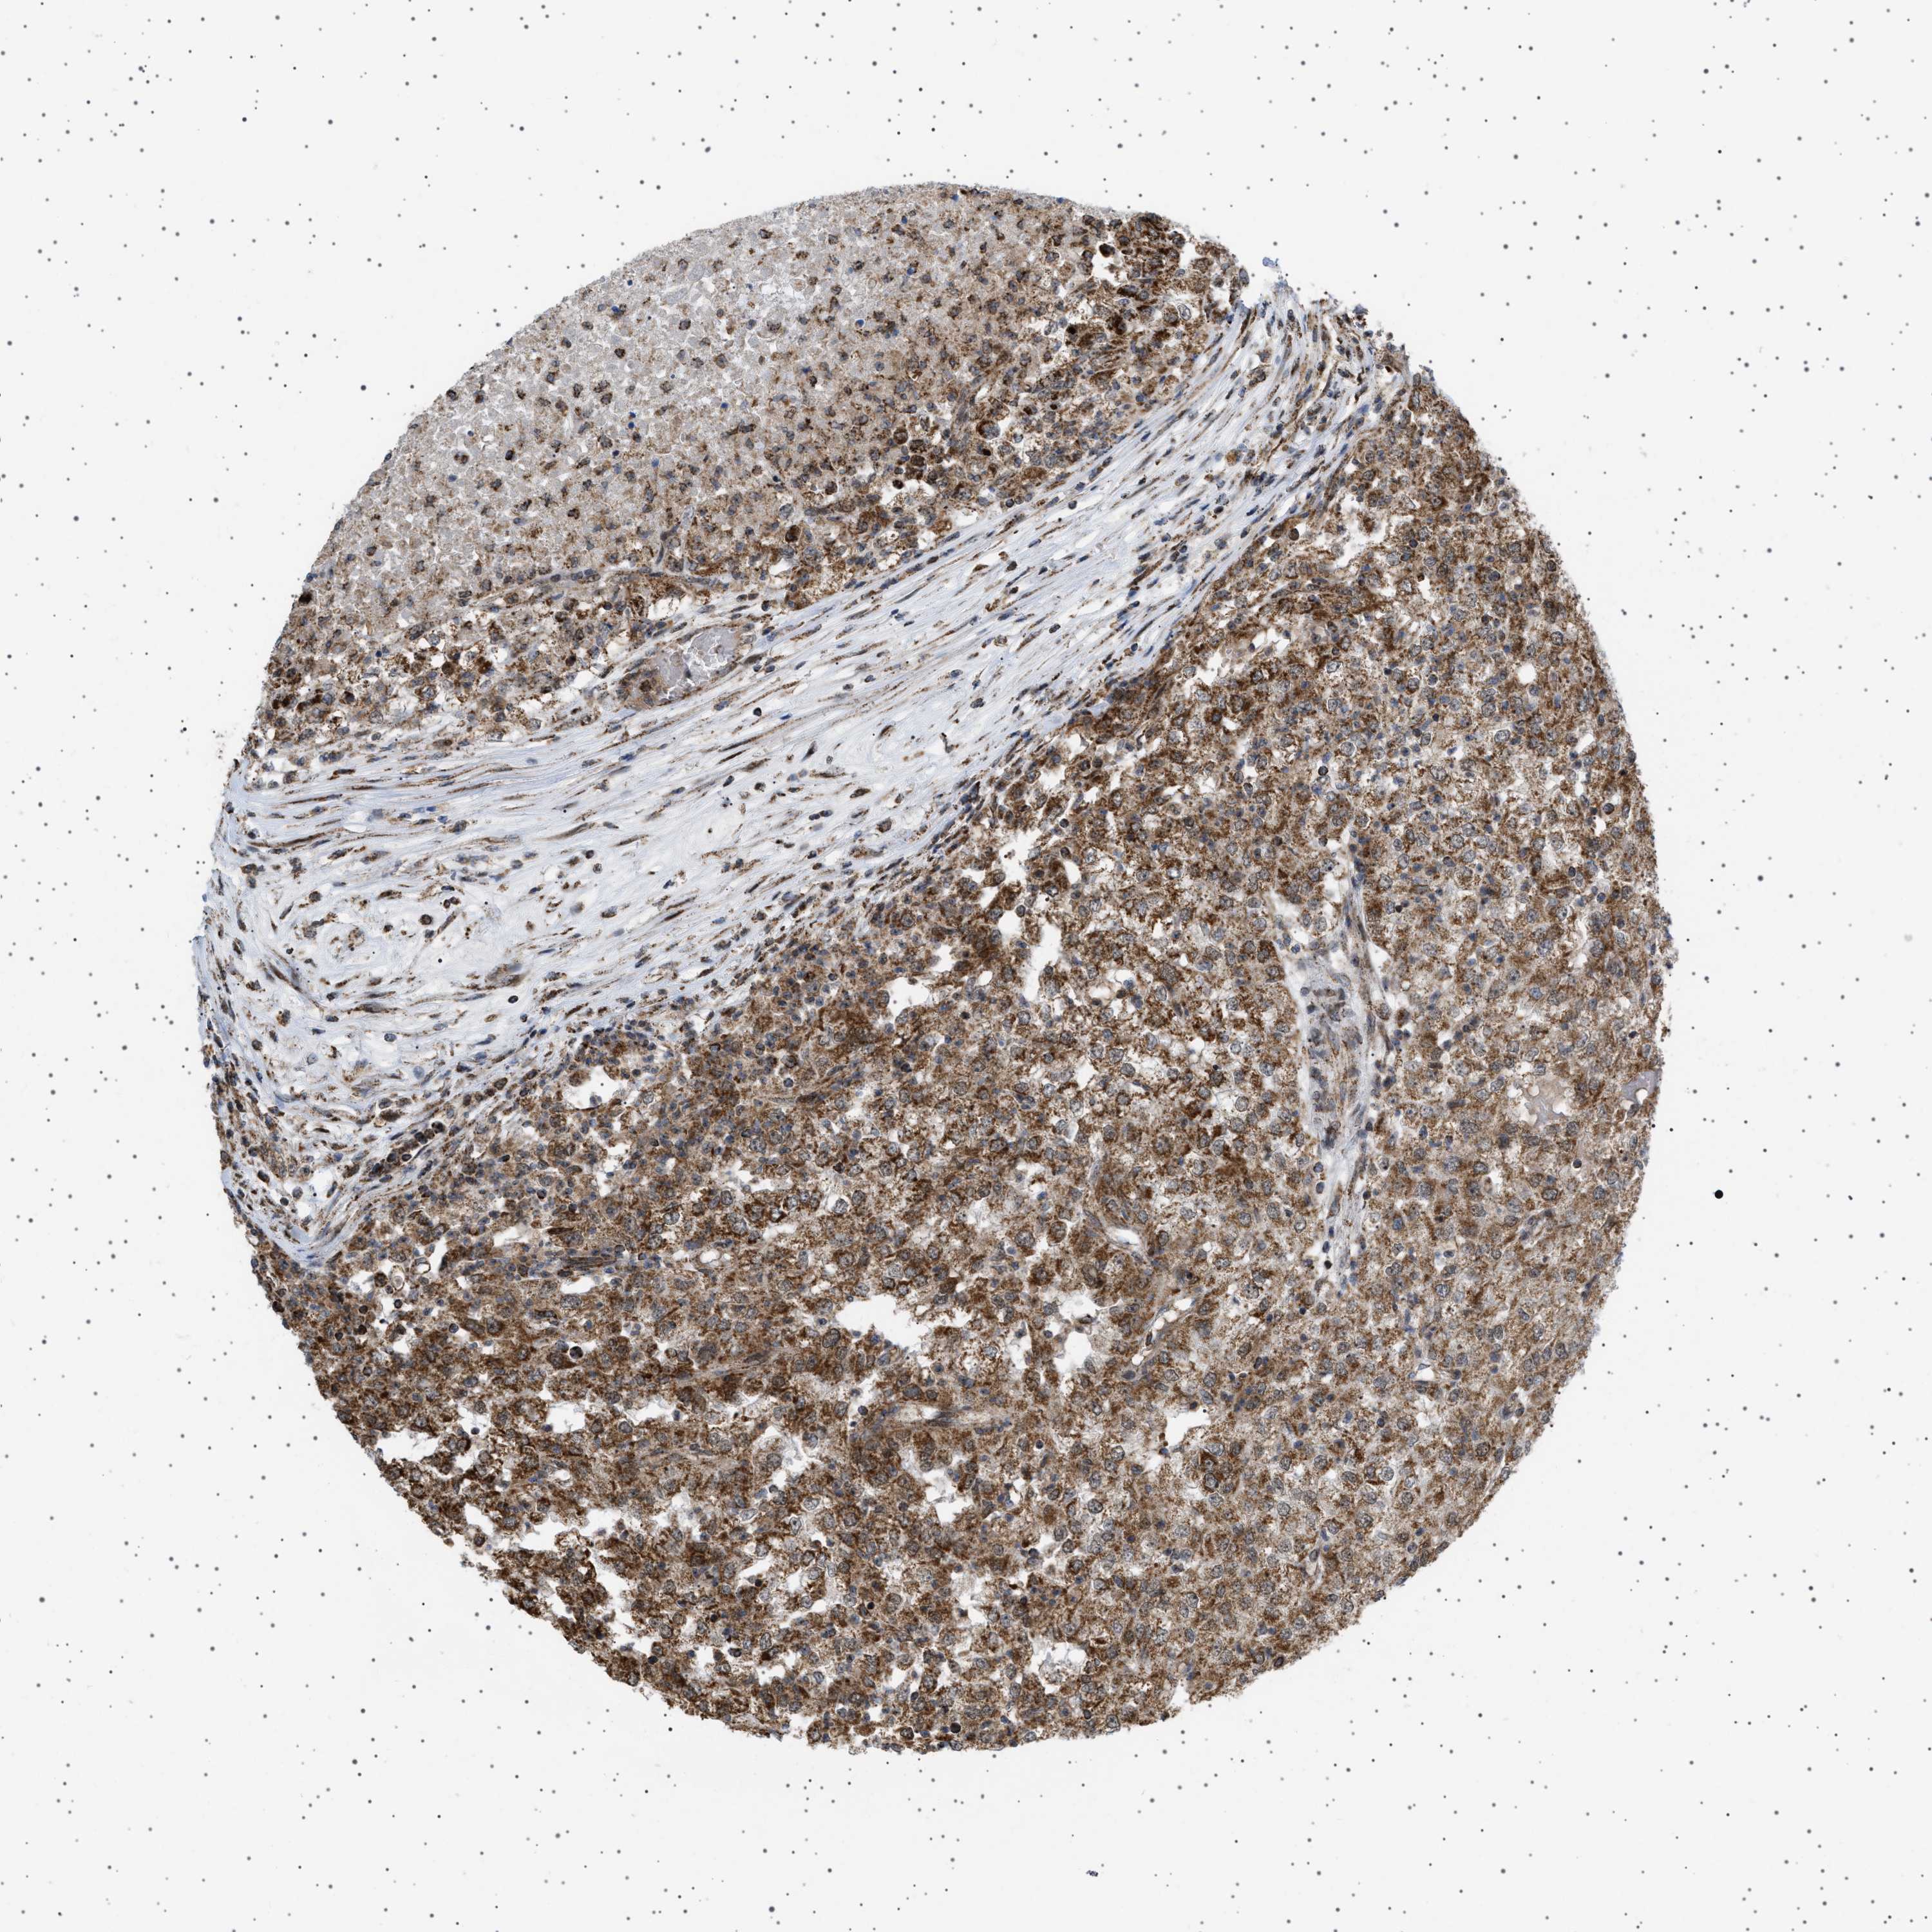

KIDNEY RENAL CLEAR CELL CARCINOMA (TCGA) - Interactive survival scatter ploti

The Survival Scatter plot shows the clinical status (i.e. dead or alive) for all individuals in the patient cohort, based on the same data that underlies the corresponding Kaplan-Meier plots. Patients that are alive at last time for follow-up are shown in blue and patients who have died during the study are shown in red.

The x-axis shows the expression levels (FPKM) of the investigated gene in the tumor tissue at the time of diagnosis. The y-axis shows the follow-up time after diagnosis (years). Both axes are complimented with kernel density curves demonstrating the data density over the axes. The top density plot shows the expression levels (FPKM) distribution among dead (red) and alive patients (blue). The right density plot shows the data density of the survived years of dead patients with high and low expression levels respectively, stratified using the cutoff indicated by the vertical dashed line through the Survival Scatter plot. This cutoff is automatically defined based on the FPKM cutoff that minimizes the p-score. The cutoff can be changed by dragging the vertical line or by entering a cutoff value in the square labeled "Current cut-off".

Under the Survival Scatter plot the p-score landscape (black curve; left axis) is shown together with dead median separation (red curve; right axis). Dead median separation is the difference in median mRNA expression between patients who have died with high and low expression, respectively. It is calculated as follows: median FPKM expression of dead patients with high expression - median FPKM expression of dead patients with low expression. This is intended to aid the user in visually exploring custom cutoffs and the associated p-scores and dead median separation.

Individual patient data is displayed and can be filtered by clicking on one or more of the category buttons on the top of the page. Categories describing expression level and patient information include: high, low, alive, dead, female, male and tumor stages. The scale of the x-axis can be toggled between linear and log-scale by clicking on the "x log" button. Mouse-over function shows TCGA ID, patient information and mRNA expression (FPKM) for each patient.

& Survival analysisi

Kaplan-Meier plots summarize results from analysis of correlation between mRNA expression level and patient survival. Patients were divided based on level of expression into one of the two groups "low" (under cut off) or "high" (over cut off). X-axis shows time for survival (years) and y-axis shows the probability of survival, where 1.0 corresponds to 100 percent.

MELK is validated prognostic, high expression is unfavorable in Kidney Renal Clear Cell Carcinoma (TCGA)

: 2.43

Average pTPM 2.1

Number of samples 521